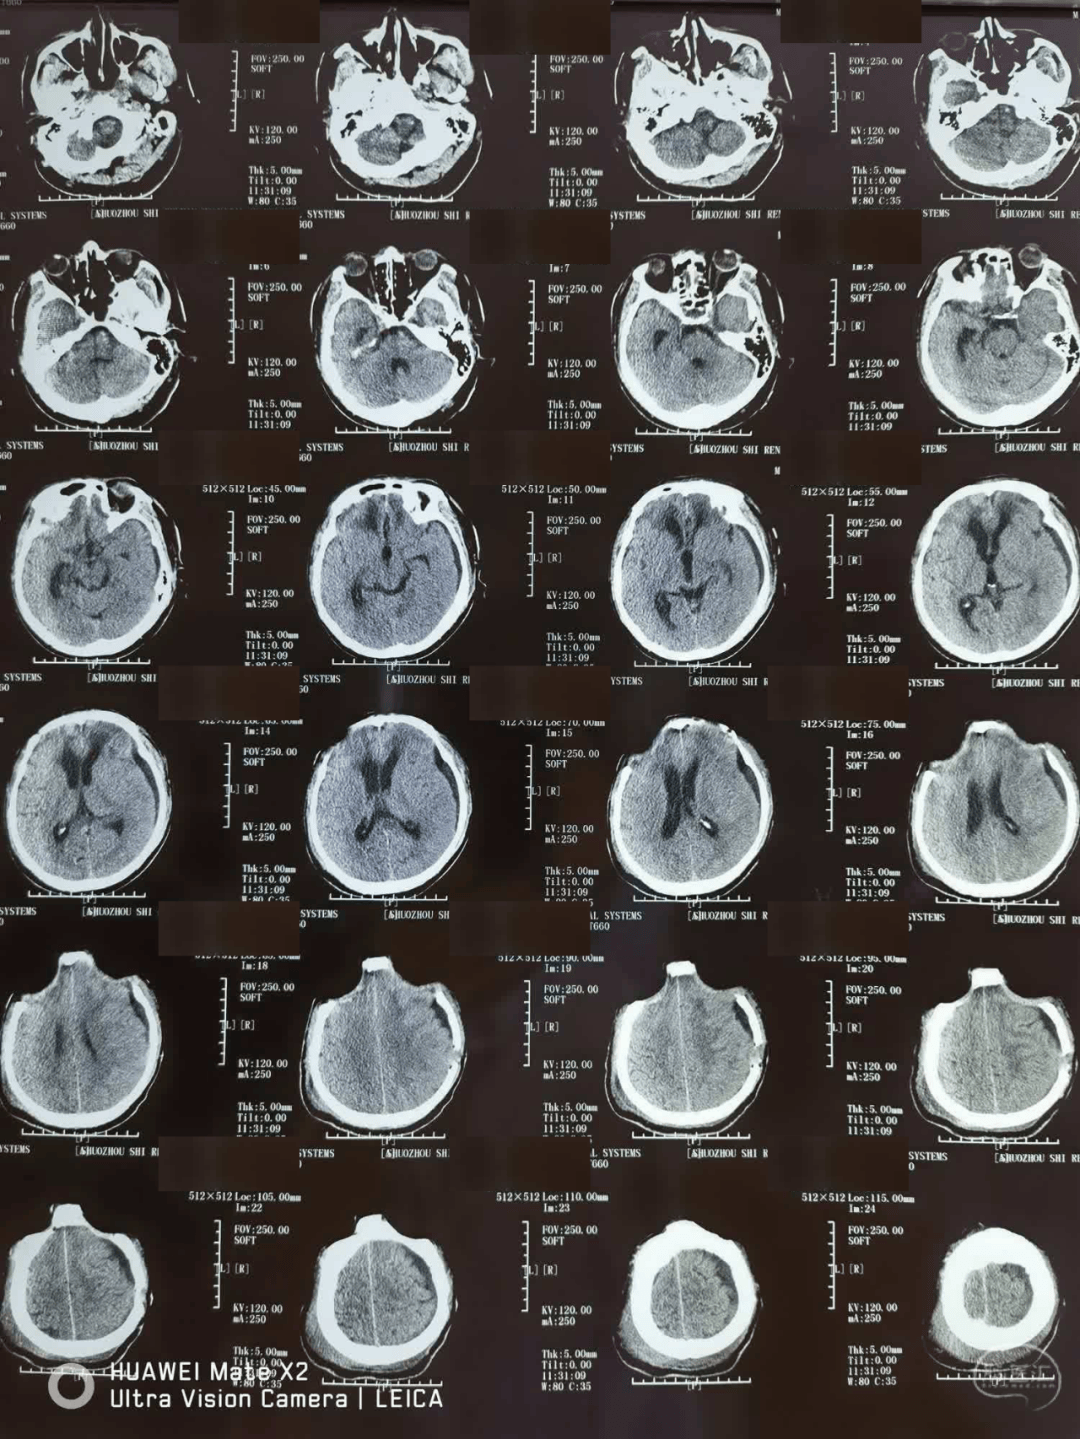

急送至安徽省某三甲医院,查头颅ct示蛛网膜下腔出血

7月31日拔除引流管,8月1日ct如下:7月28日ct,引流减少,夹闭引流管